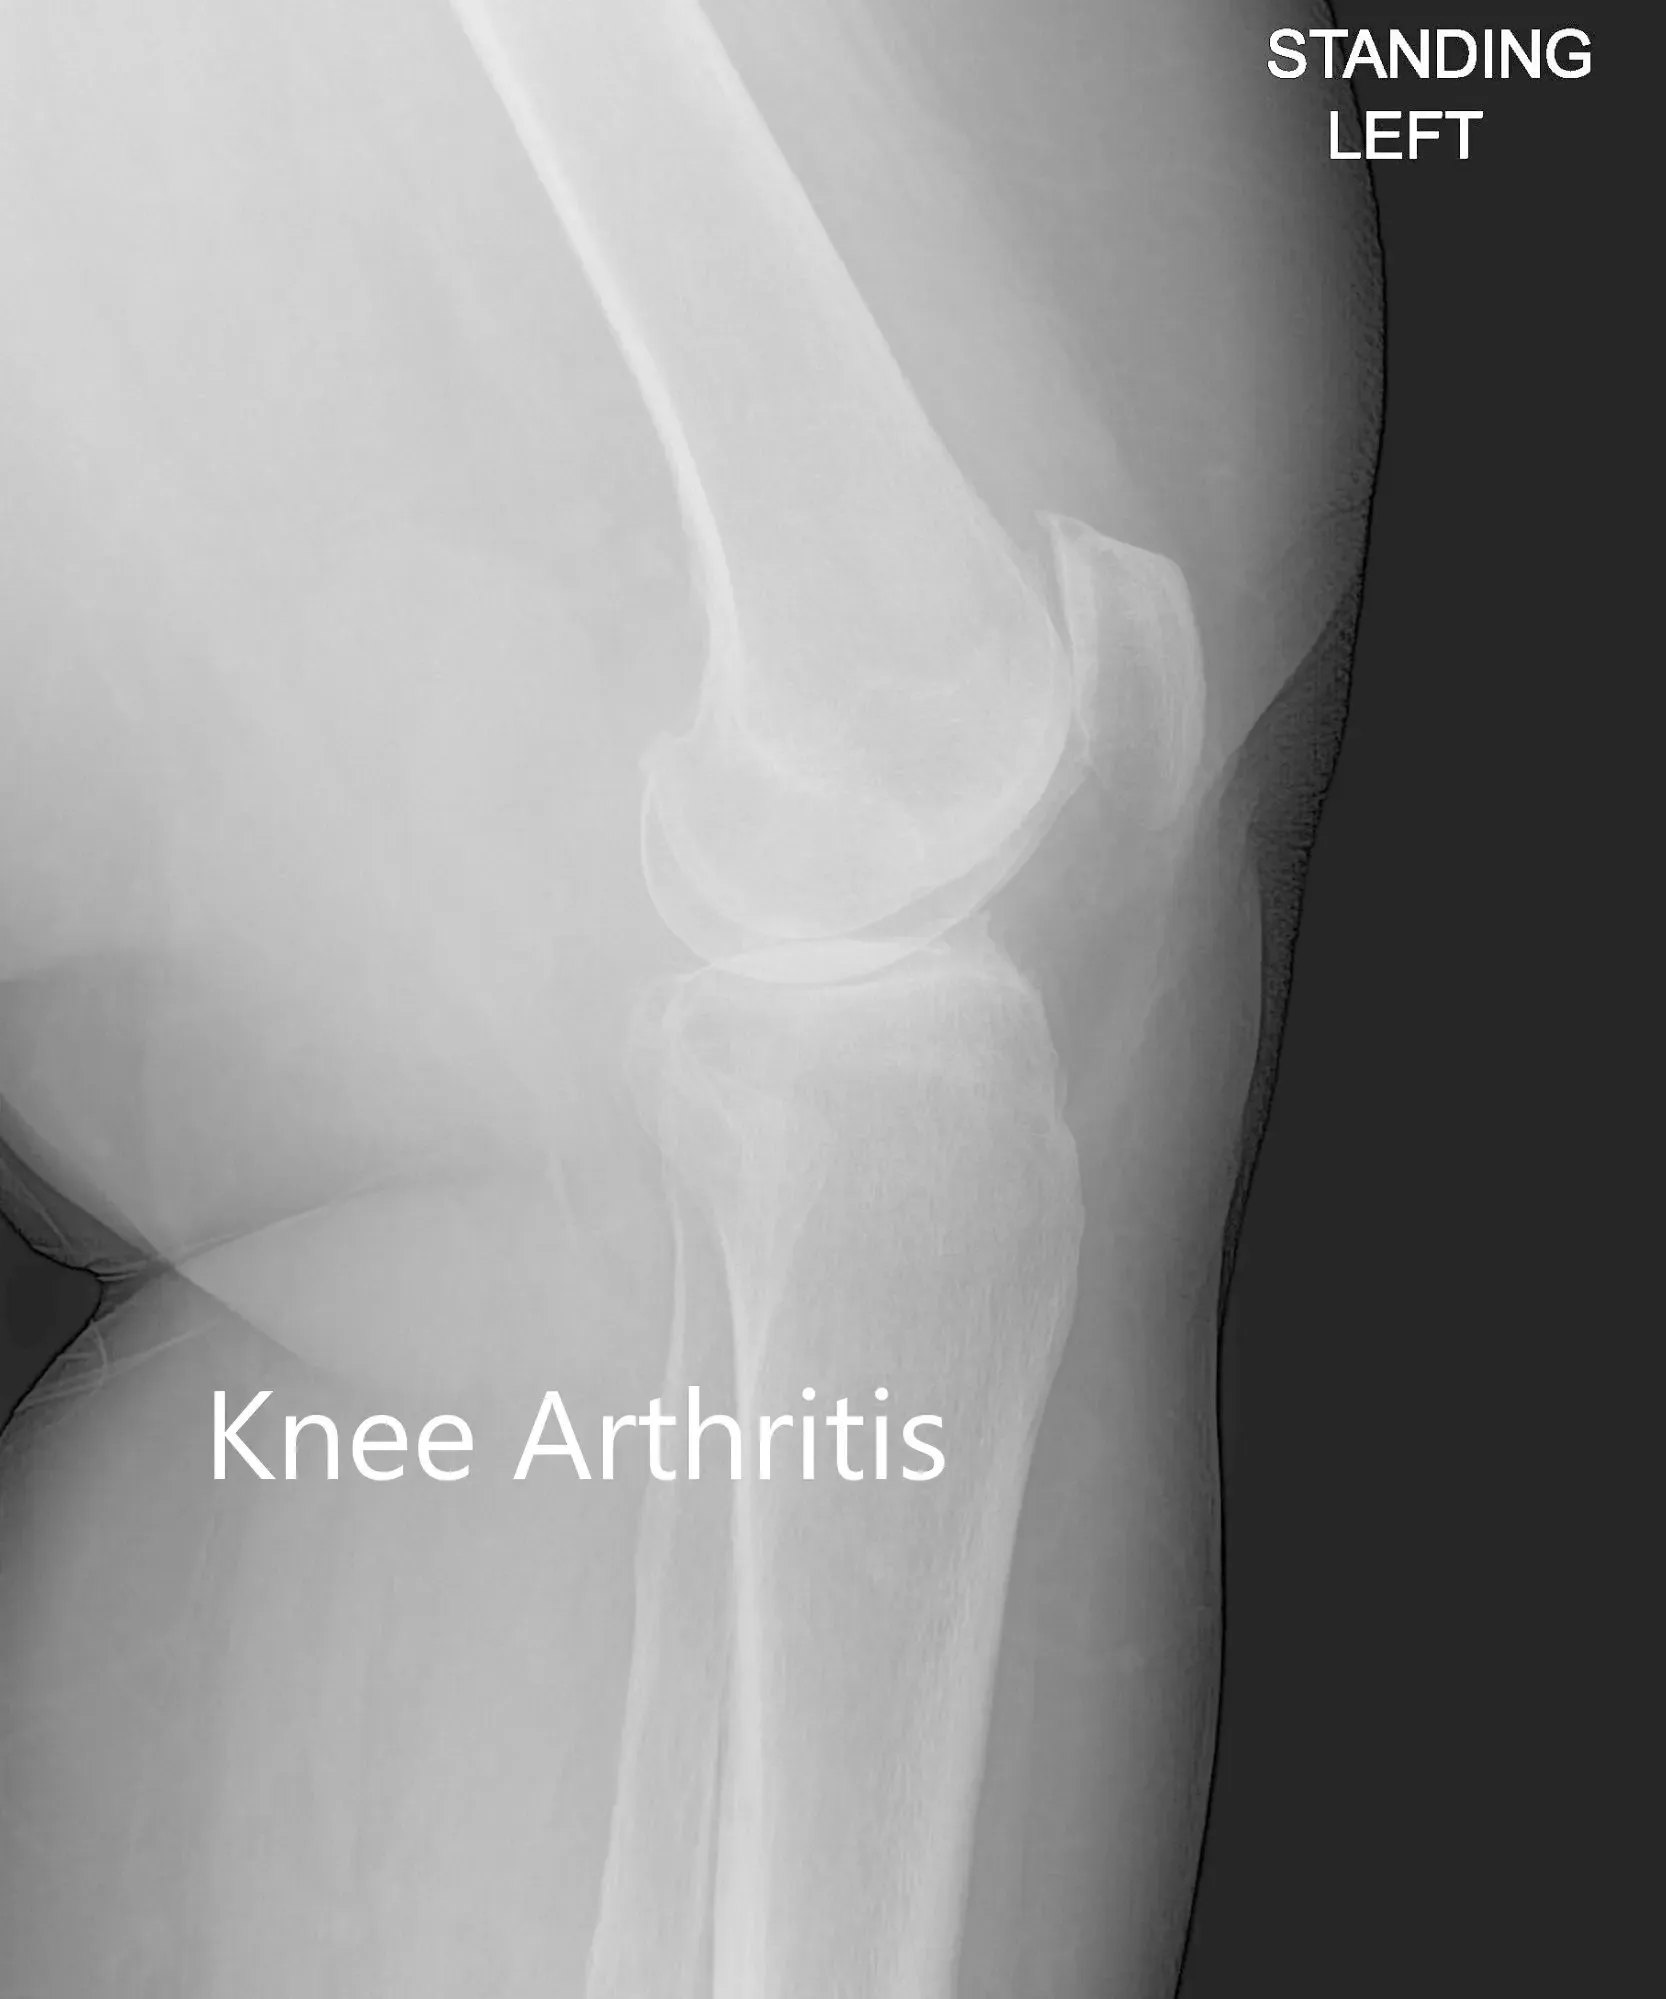

Las imágenes revelaron osteoartritis tricompartmental severa de la rodilla izquierda con reducción del espacio articular y osteófitos.

Vista anteroposterior y lateral de la rodilla izquierda